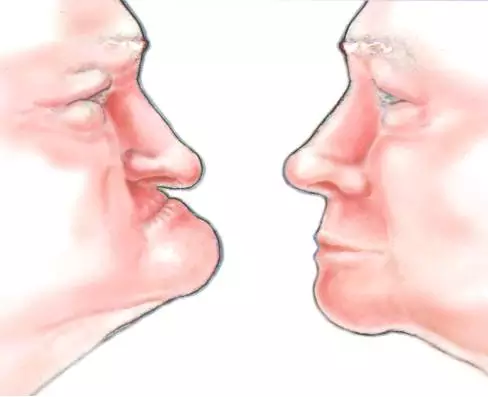

如果牙齿长时间缺少牙根的支撑,牙槽骨将会严重萎缩造成牙弓走位,且支撑脸型的能力也会降低,脸部会跟着改变,比同龄人显得苍老。

所以牙齿出现缺失时候,一定要及时修复,以免造成更严重的后果。